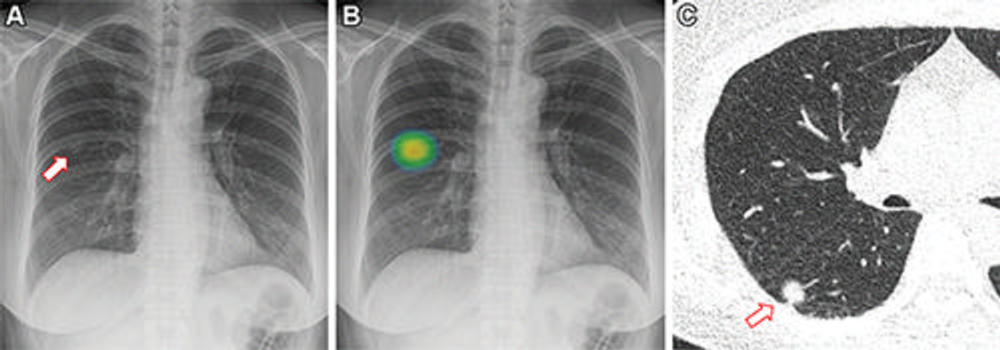

Figure 2. Frontal chest X-ray shows a small nodular opacity (arrow) in the left upper lung zone. Axial, non-contrast, low-dose chest CT scan shows a 9-mm solid nodule (arrow) in the left upper lobe.